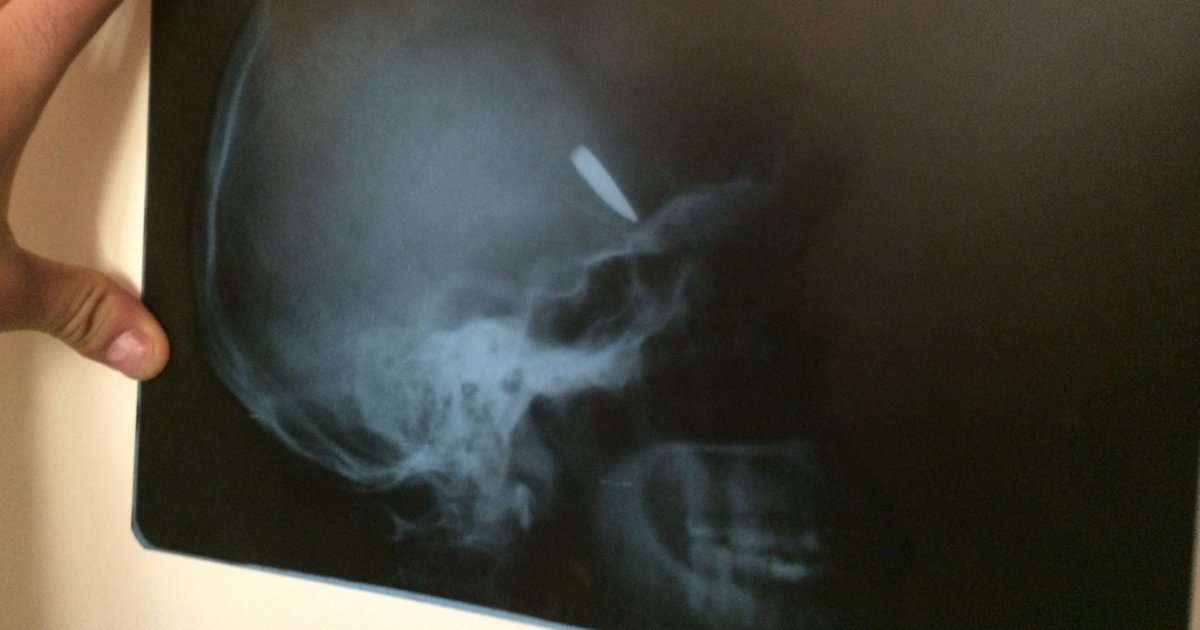

По информации автора, боец "Миротворца", Саша Ковальчук 29-го августа, как и все, выезжал из Иловайска и попал в страшную мясорубку: "Расстрел начался еще в переполненном автобусе. Во время боев одна из пуль попала в голову (!) и... застряла. Саша лежал под забором в окрестностях Старобешево и истекал кровью. По счастливому стечению обстоятельств, его вывезли в Донецк, где в местной больнице врач провел тяжелейшую операцию и вытащил кусок металла из его головы. Позже, также по благосклонности судьбы, Саша был обменен и вернулся на украинскую территорию, в Днепропетровский госпиталь, потом - в госпиталь МВД в Киеве".